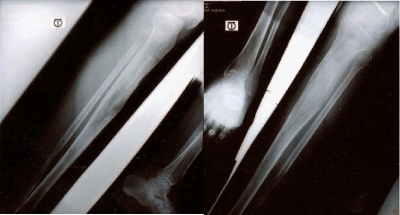

Figure 1 40 yrs old male, 19 yrs of Non-union left femur due to gunshot injury, 13 cm shortening; before surgery.

Figure 2 Radiograph of non-union of left femur with gunshot injury.